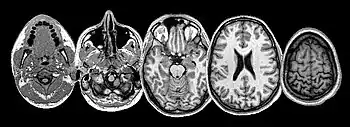

Central nervous system

The nervous system is composed of a central nervous system (CNS), brain and spinal cord, and the peripheral nervous system (PNS), cranial nerves and spinal nerves. The CNS is located within the dorsal cavity, and the PNS extends through the ventral cavity. The central nervous system provides control and coordination of all eleven body systems and utilizes the endocrine system to form hormone chemical messengers that transport through the blood to influence the activity of individual cells of the body and their associated tissues, organs and systems.

The CNS is protected by the cranium, vertebral column, meninges, cerebrospinal fluid. The spinal cord is an extension of the brain. The spinal cord and the brain stem are joined at the base of the cranium at the foramen magnum. Most of the functions of the head and neck are directly influenced by the brain and transmitted to the PNS via the cranial nerves and spinal nerves of the cervical portion of the spine.